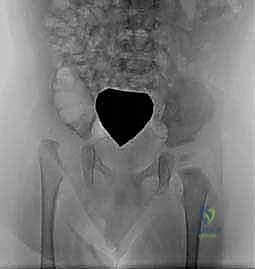

2. الأشعة السينية (X-Rays)

عندما يبلغ الطفل 6 أشهر فما فوق، تبدأ مراكز التعظم في الظهور في رأس الفخذ. في هذه المرحلة، تصبح الأشعة السينية ضرورية وأكثر دقة من الموجات فوق الصوتية.

يقوم الأستاذ الدكتور محمد هطيف بتحليل دقيق للأشعة السينية، حيث يرسم خطوطاً وهمية (مثل خط هيلجينراينر وخط بيركين) لتحديد موقع رأس الفخذ بدقة، وقياس "مؤشر الحُق" (Acetabular Index) لمعرفة مدى ضحالة التجويف. هذه القياسات حاسمة لتحديد ما إذا كان الطفل يحتاج إلى جراحة أم لا.